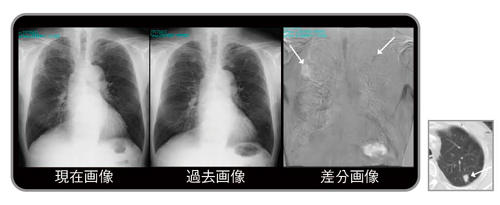

図1 差分画像の見え方

1980年代に商品化されたデジタル画像は,その後急速に普及し,2010年代の今ではほとんどの医療用画像はデジタル化され,モニタにより診断や治療が行われている1)。本稿で紹介する経時的差分法(temporal subtraction:TS)は,現在画像から過去画像を自動的に引き算して,変化のあった病変のみを強調して表示する手法で,新しく出現した病変を黒く表示し,消失した病変は白く表示させることで読影を支援するシステムである(図1)。

左上肺野の小結節出現(黒く表示),右中肺野の肺炎消失(白く表示)

従来の比較読影に,さらに差分画像を追加することにより,正常肺構造や既存肺病変に隠れがちな新規病変は,病変のみが明瞭に描出されるようになるため,読影時の気づきに大きな貢献が期待できる。また,従来の読影法のように一か所ごとに病変を見比べるのではなく,差分画像を一瞥するだけで胸部全体の変化のある病変だけを把握でき,読影時間の短縮につながることが期待できる。